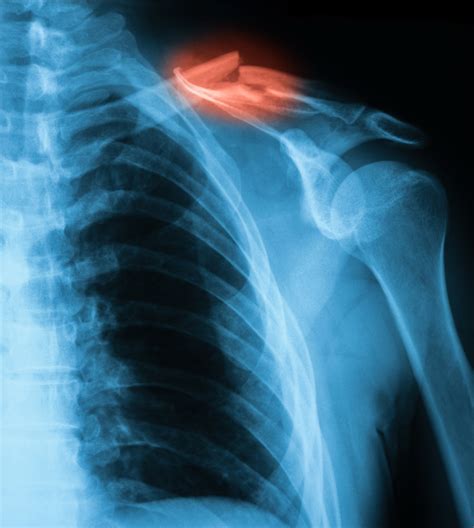

In more severe cases, the bone may be broken into several pieces. It's understandable why an inquiring mind would want to know, but unfortunately a collarbone or clavicle fracture involves one of the main bones in the shoulder.

Some complicated fractures may need surgery and surgical traction. The most common broken bones are stress fractures, rib fractures, skull fractures, hip fractures, and fractures in children. There are different causes and types of fractures.

People typically do not know that they have osteoporosis until their bones become so weak that a sudden strain, twist.

Hospitalization for anesthesia and treatment of severe fractures. Treatment includes immobilising the bone with a plaster cast, or surgically inserting metal rods or plates to hold the bone pieces together. There are different causes and types of fractures. Hospitalization for anesthesia and treatment of severe fractures. A fracture, simply put, is a broken bone. A bone break is often a sudden, painful indicator of osteoporosis. Compound fractures are considered much more serious than simple fractures because they may be complicated by deep infections if pathogens enter the body through the wound. A fracture is a partial or complete break in the bone. A fracture to the fifth metacarpal bone is much rarer injuries first. The femur is the strongest bone in the body, and although i haven't broken it (yet), i know 2 people that have, and its the most painful bone to break. We explain what leads to a but if your bones are especially brittle, you may experience little pain and not even know you have buckle fracture: Both bones forearm fractures are most commonly treated by placing a metal plate and screws on both the radius and ulna bones. Bones are far from invincible, however, and a blow with enough force at the right angle can cause a bone to break. While mild strains and sprains of ligaments and muscles can often be treated at home, fractures typically require you can usually tell that you have a broken bone because the area is much more swollen or painful than it would be with a less severe injury. It makes bones fragile and more prone to fractures, especially the bones of the hip, spine, and wrist. Fracture healing in a broken bone is quite a complex process and includes interplay of many factors but let us make it simple and understandable. Most broken collarbones occur when the person falls onto their.